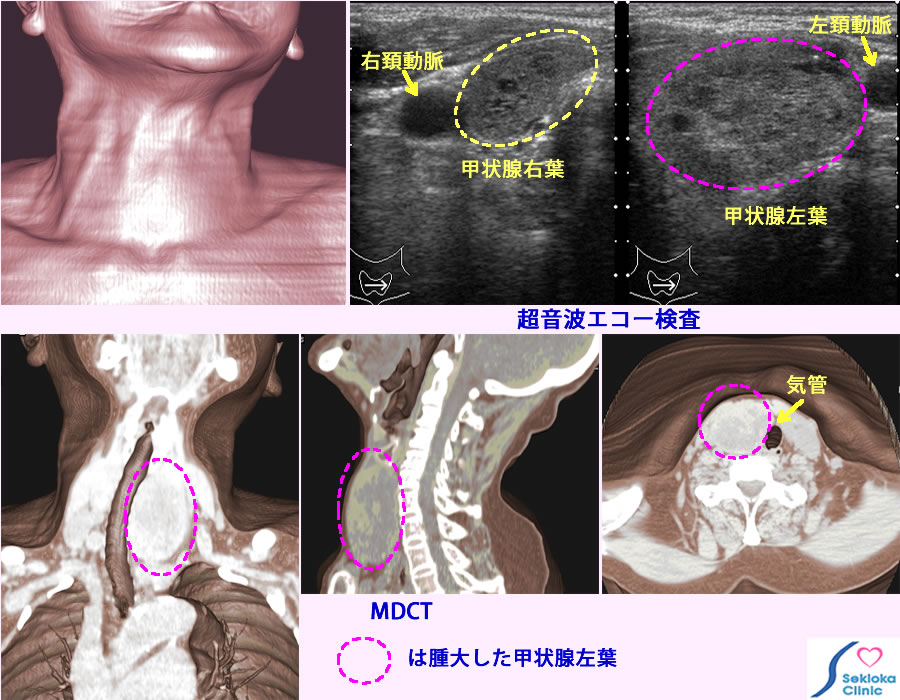

| 診断 | 症状に対して甲状腺の機能亢進や低下が原因として疑われる場合、即ち、バセドウ病や慢性甲状腺炎などや単純性甲状腺腫など腫大の病因鑑別のためには、甲状腺ホルモン、甲状腺刺激ホルモン、甲状腺刺激ホルモン受容体抗体、甲状腺組織に対する各種抗体などを測定してそれらの組み合わせから病態を推定します。甲状腺の腫大がある程度大きい場合は触診、視診でもわかります。詳細な評価は超音波エコー検査をを行います。大きさ評価だけでなく、、甲状腺の内部構造から、びまん性腫大(多くは良性腫大)、がん(結節性病変で周辺の不規則な形状、石灰化、低エコーなどの所見)、のうほうなどを鑑別します。良性か、がんの鑑別が難しい場合は細い針を異常部位に刺して、吸引細胞診という方法で細胞を顕微鏡で検査します。組織性状・機能評価のため放射性ヨード摂取率を用いた画像診断も行われます。甲状腺腫大が著しい場合はその広がりを知るため、CT、MRI検査なども行いまず。 |

| 治療 | がんの場合は基本的に手術。良性腫大で機能亢進のみの場合は年齢などを考慮してアイソトープ治療、手術、抗甲状腺薬による治療など選択されます。供覧の画像は甲状腺の著明な腫大を認め、気管の圧迫もあるため、甲状腺腫全体の広がり部位を3次元的に評価するためMDCT検査を行ったものです、吸引細胞診では悪性所見は認められず、年齢、患者さんの意向を考慮して 抗甲状腺剤で甲状腺機能の正常化を得ました。治療前は痩せ、手の振戦、動悸がありました。 |